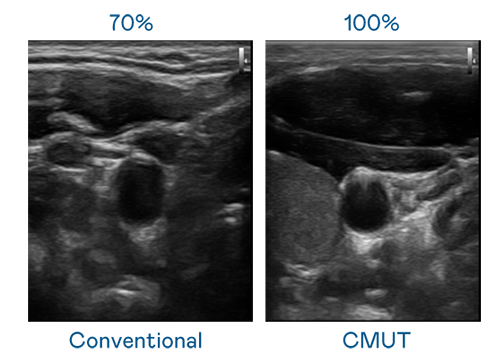

CMUT 技术是一种用电容式微机电元件来产生超音波讯号的技术。与传统 PZT 压电式技术相比,CMUT 频宽增加 30%,更宽频的超音波讯号让影像解析度大幅提升,是实现高影像品质医疗超音波扫描、促进精准医疗发展的关键技术。

超音波影像的解析度高低,首先取决于探头能发出的讯号频宽。AG旗舰厅 CMUT 可提供高清晰的超音波讯号,提供高频宽、高灵敏度、影像纹理细节更高的超音波影像,协助医护人员缩短影像判读时间及利用精准的医疗影像进行诊断。